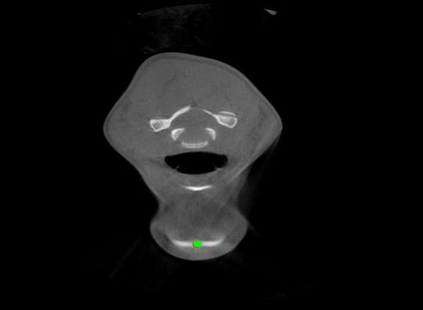

Detecting 3D landmarks on cone-beam computed tomography (CBCT) is crucial to assessing and quantifying the anatomical abnormalities in 3D cephalometric analysis. However, the current methods are time-consuming and suffer from large biases in landmark localization, leading to unreliable diagnosis results. In this work, we propose a novel Structure-Aware Long Short-Term Memory framework (SA-LSTM) for efficient and accurate 3D landmark detection. To reduce the computational burden, SA-LSTM is designed in two stages. It first locates the coarse landmarks via heatmap regression on a down-sampled CBCT volume and then progressively refines landmarks by attentive offset regression using multi-resolution cropped patches. To boost accuracy, SA-LSTM captures global-local dependence among the cropping patches via self-attention. Specifically, a novel graph attention module implicitly encodes the landmark's global structure to rationalize the predicted position. Moreover, a novel attention-gated module recursively filters irrelevant local features and maintains high-confident local predictions for aggregating the final result. Experiments conducted on an in-house dataset and a public dataset show that our method outperforms state-of-the-art methods, achieving 1.64 mm and 2.37 mm average errors, respectively. Furthermore, our method is very efficient, taking only 0.5 seconds for inferring the whole CBCT volume of resolution 768$\times$768$\times$576.